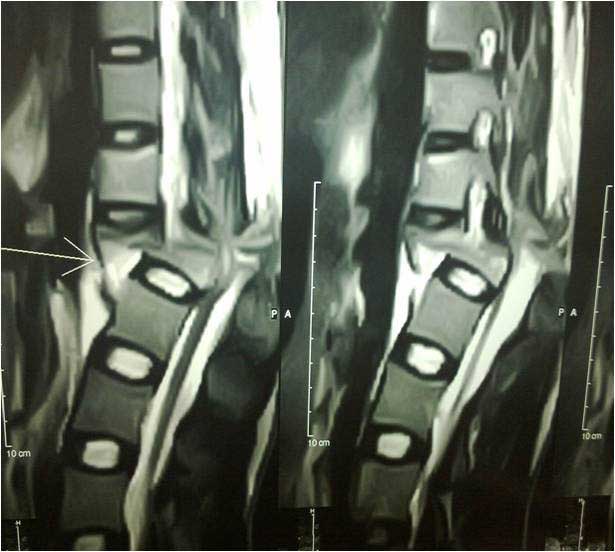

PRE OP MRI SPINE INJURY

Spine Fixation Lumbar Spine